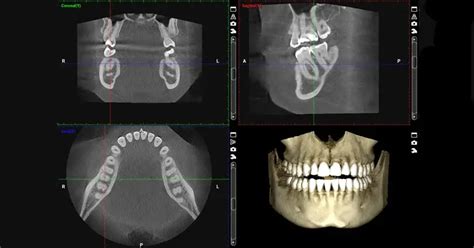

La tomografía computarizada de haz cónico (CBCT, del inglés Cone-Beam Computed Tomography) ha tenido una amplia aceptación en los últimos años en gran parte de las especialidades odontológicas, incluyendo ortodoncia. Esto, debido a que la CBCT entrega una imagen tridimensional que permite obtener imágenes en todos los planos del espacio.

Adicionalmente, en las imágenes de CBCT no hay sobreproyección de estructuras como ocurre en las radiografías bidimensionales (2D). Además, las imágenes de CBCT son más precisas que la radiografía 2D, es decir, las estructuras anatómicas se reproducen en su forma y tamaño real. Lo anterior facilita el diagnóstico y planificación del tratamiento.

La exploración mediante tac dental o tomografía computarizada para el diagnóstico maxilofacial debe ser efectuada con equipos que dispongan de programas informáticos de reformación multiplanar (MPR).

El desarrollo de la CBCT como técnica de diagnóstico bucofacial representa un cambio radical de la radiología dental y maxilofacial, ya que acerca la tomografía computarizada a la práctica clínica diaria. El éxito de la CBCT se debe a que ha facilitado de forma generalizada la transición de las imágenes radiográficas, en el diagnóstico odontoestomatológico, desde el 2D al 3D.

Las imágenes sagitales y coronales ofrecen una excelente representación del espacio articular y permiten detectar la presencia de patologías. Dada la alta calidad y precisión de las imágenes, se puede llevar a cabo una correcta evaluación anatómica de la ATM.

Con el CBCT es posible visualizar claramente las vías aéreas, las estructuras del oído interno, los peñascos, las mastoides y los senos paranasales.